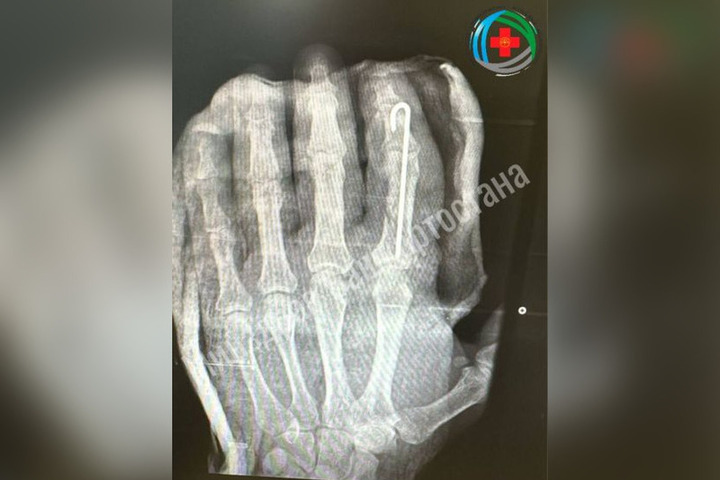

В Благовещенске врачи провели операцию по восстановлению ампутированного из-за травмы пальца.

Мужчина при работе с топором нанес неосторожный удар и лишился пальца. Врачи приняли решение провести экстренную операцию. Хирурги сшили мельчайшие сосуды, зафиксировали кости и провели реконструкцию мягких тканей.

Палец прижился, и пациент уже начал двигать им, проходя восстановительное лечение.